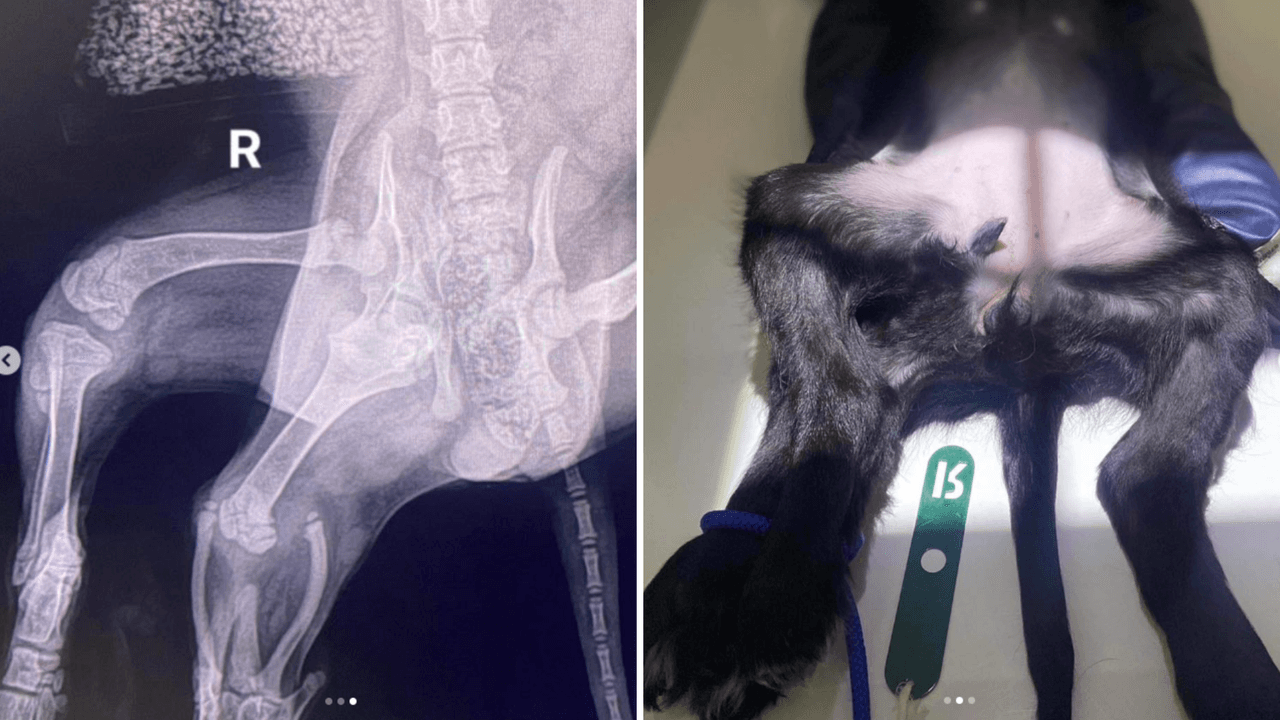

Greenacres Rescue publicó en sus redes sociales un par de imágenes de la cachorra y lo que la diferenciaba: nació con seis patas.

El 29 de septiembre pasado, tras una visita a especialistas, el refugio de animales informó que “todos” los órganos de Ariel “están donde deberían estar” y que ella tenía “dos patas traseras adicionales y los inicios de una vulva adicional. Su pelvis no se ha formado bien debido a que también tiene una articulación de cadera extra”.

Estas malformaciones no le impedían caminar, pero sí le causaban otros problemas, como poco tono muscular en la pata derecha.

Tras una larga asistencia médica, los especialistas concluyeron que podían retirar las piernas adicionales de Ariel gracias a una cirugía, que se tiene planeada para el próximo 17 de enero.